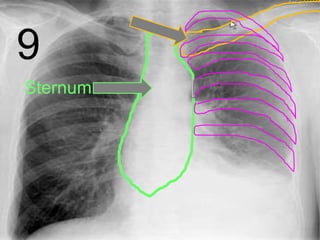

• Your skeletal system surrounds your most

important internal organs with a rib cage.

Sternum